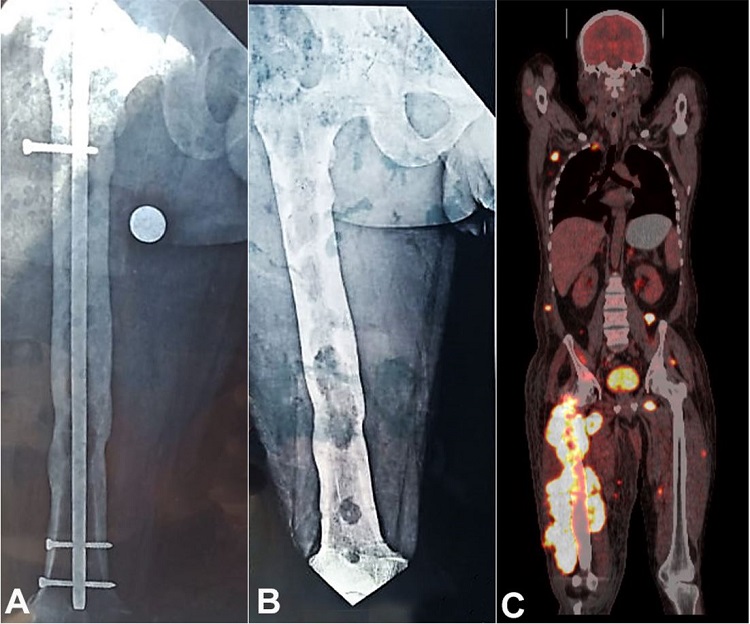

A 42-year-old man presented with the complaint of painful swelling in the right lower limb for 5 months. Also, he noted a serous discharge from the scar of the previous surgery, over the last 5 months. His medical history included an internal fixation with a metal rod implant for femoral fracture treatment (Figure 1A). Roughly two months after the initial symptoms, the implant was removed (Figure 1B). The computed tomography (CT) detected a huge right proximal thigh lesion as well as multiple soft tissue lesions. These soft tissue lesions included the subcutaneous tissue of the face and abdominal wall, left perinephric and posterior pararenal space, left gluteal region, right second rib, and the right iliac bone. The Magnetic resonance imaging (MRI) scan of the right thigh showed an ill-defined, lobulated, expansile, intramedullary lytic lesion, which involved the metaphyseal and diaphyseal region of the femur. It also showed thickening and multi-focal breach of the cortex with associated extraosseous soft tissue component involving the skeletal muscle tissue. The positron emission tomography (PET) showed increased FDG avid uptake in the right thigh, nodal and extranodal tissue, intramuscular and subcutaneous region, renal, bowel, skeletal, omental, and peritoneal region, indicating the possibility of a disseminated malignancy (Figure 1C).